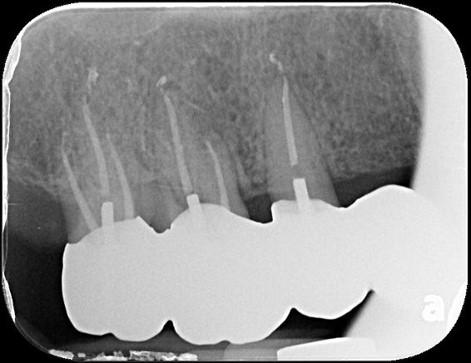

治療前,第一大臼齒根尖病變

顯微根管重治療